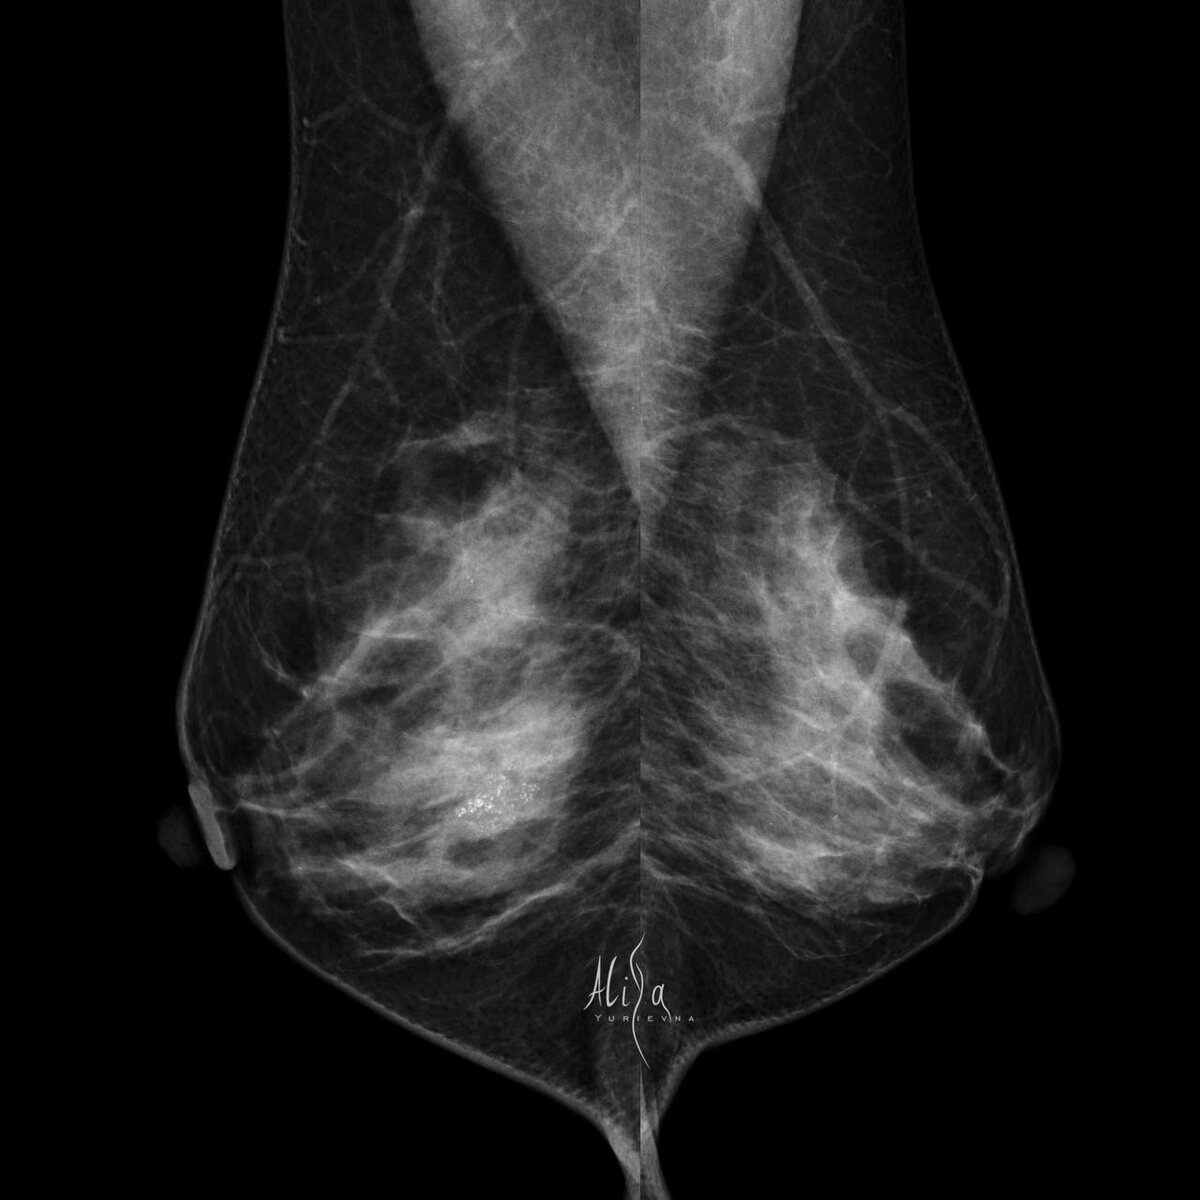

Женщина 41 год  Жалоб нет. Первая маммография.  История практически ежедневная. Что поможет не пропустить патологию? Правильное, последовательное выполнение методик.  Сначала — маммография, потом УЗИ.  Такие кальцинаты достаточно хорошо видны при УЗИ, если ваш мозг знает, ЧТО искать и КАК они будут выглядеть.  И биопсию, кстати, вы здесь тоже легко выполните под узи контролем.  Гистология: cTis (dcic)cN0cM0 Морфологическая картина представлена карциномой in situ high grade.

Женщина 41 год

Жалоб нет. Первая маммография.

cTis (dcic)cN0cM0 Морфологическая картина представлена карциномой in situ high grade.